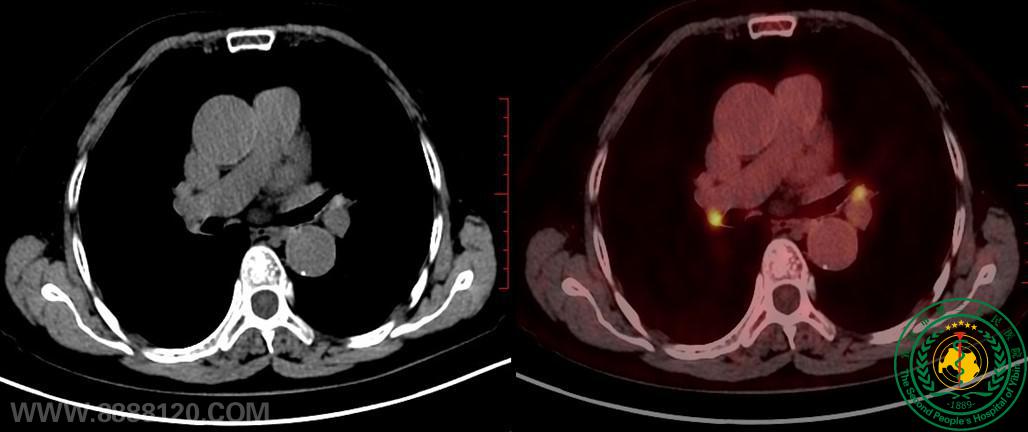

(图3 纵膈及双肺门炎性淋巴结CT密度增高,FDG代谢增高)

检查前,核医学科医师对患者进行了详细问诊、检查流程告知和检查注意事项交代。在注射完显像药物18F-FDG并安静 1小时后,患者上机完成了头颅及躯干PET/CT扫描,历时约15分钟。此次检查填补了大型医用设备高端检查在宜宾医学领域的空白,达到了省内先进水平,满足了广大群众的诊疗需求和就医便利性。本次一共进行了5名患者的18F-FDG PET/CT检查,CT解剖图像及PET代谢图像均显像异常清晰,融合完美,全面显示了患者的所有病灶,标志着宜宾地区从此进入医学分子影像新时代。